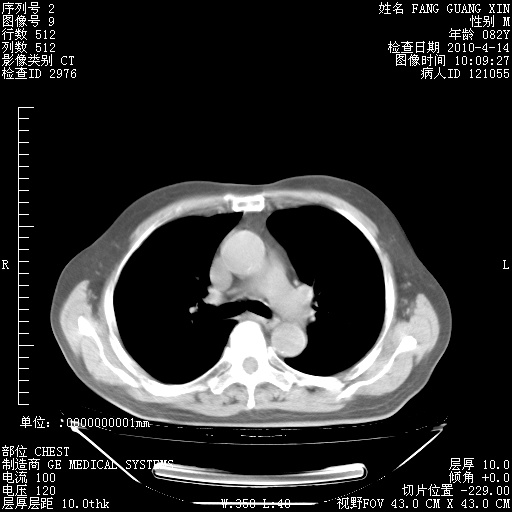

4月14日肺部CT

23.JPG

24.JPG

25.JPG

26.JPG